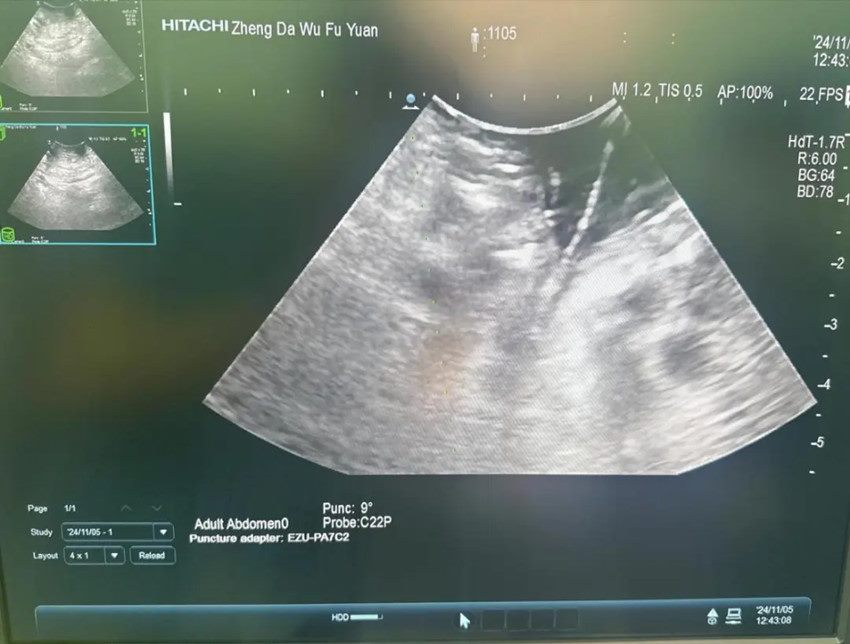

经过积极术前准备,在手术部•麻醉科胡强夫主任麻醉团队及手术室刘丹丹护士长护理团队的配合下,由陈艳军主任主刀,程冰冰主治医师,李想医师作为助手的手术团队为患者实施胰腺癌纳米刀消融术。术中精细分离血管组织,充分暴露病灶,使用超声探查明确肿瘤大小、形态与周围重要结构关系,将超声探查所得数据输入纳米刀系统,制定消融方案,在超声引导下精准布针,充分暴露肿瘤组织,对其进行多角度多点消融,确保对肿瘤瘤体及周围可能浸润的组织进行充分毁损,尽可能杀灭肿瘤细胞,合理布针一次消融完成后,适当退针,多次消融完毕再次通过超声评估消融范围满意。术中实时心电监测,患者各项生命体征平稳,无明显出血。